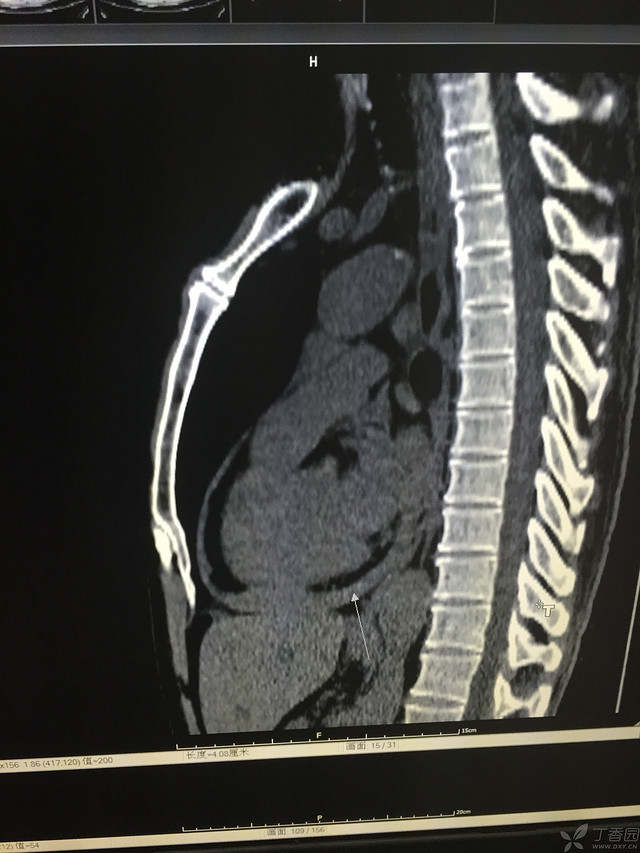

胸痛三天,加重三小时(CT是心包高密度影是什么)

患者性别:男

患者年龄:64岁

简要病史:三天前休息时突发胸前区疼痛伴大汗,到当地医院输液治疗后缓解,3小时前情绪激动后再次出现胸痛伴大汗,胸部压迫感,持续不缓解入院,到当地医院测血压180/?mmHg泵入硝酸甘油转入我院。

体格检查:血压94/72mmHg(右侧)96/74mmHg(左侧),心率78此/分,其他未见阳性体征